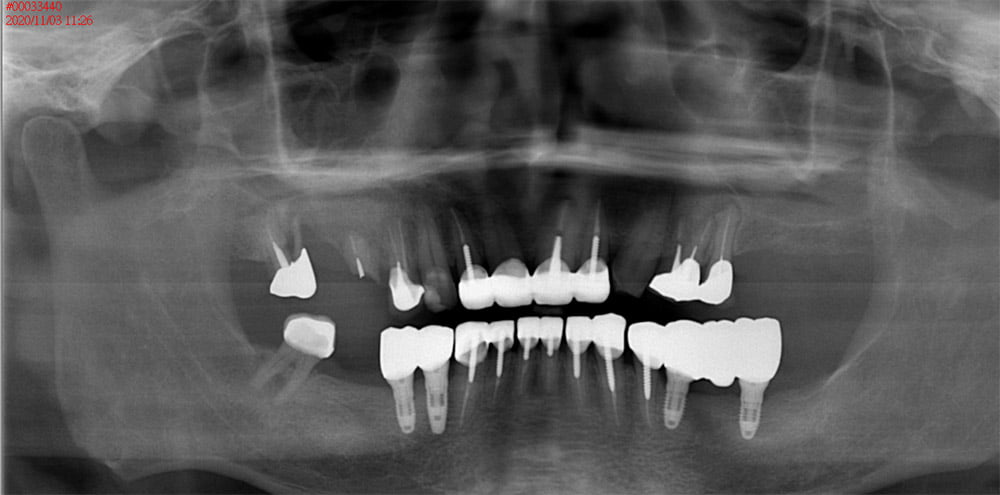

全口重建

牙齒矯正

隱適美

人工植牙